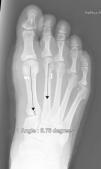

The 36 feet treated with this technique were evaluated and improvement of the IMA was achieved from 13.8° (range: 11–16°) to 7.6° in the immediate post-operative (range: 7–10°) with a mean improvement of this parameter of 6.2° (p<0.01). The HVA improved from a mean pre-operative value of 26.8° (range: 19–34°) to a mean value in the immediate post-operative period of 13.7° (range: 12–20°), showing a mean improvement of 13.1° (p<0.05). The results obtained at 15 days did not differ from the initial outcomes, although the results obtained starting at week 6 did improve, when the mean post-operative IMA was 8.6° and the HVA, 15.2°, with mean losses of 1° and 1.5°, respectively, in reduction. The values obtained at 3 months reveal a mean IMA of 9° and HVA of 16.2°, i.e. a loss of 1.4° in correction with respect to the initial IMA and 3.5° insofar as the initial HVA is concerned. At the 6-month, 1-year, and final follow-up visits, there were no variations as regards the IMA, but the HVA at the 1-year follow-up was 16.8° (Table 1). Therefore, there was an overall improvement at the final follow-up visit of 4.8° in the IMA (p<0.05), having lost 22% of the initial gain, and 10° in the HVA (p<0.05), having lost 27% of the initial gain (Table 2).

In our opinion, optimal radiological correction can be defined in terms of the initial classification (obtaining angle values within normal limits, namely IMA < 9° and HVA <11°) or in statistical terms (significant differences with a p value of at least <0.05). Insofar as the correction values obtained in this study are concerned, they demonstrate that this system makes it possible to achieve adequate correction of the IMA (both statistically and in “ideal” terms) and of the HVA (more statistical than classification, given that we manage to lessen the severity, albeit not bringing it back to normality, strictly speaking), comparable to other series that have made use of classical techniques34–36 (Table 1), although the immediate follow-up (up to 3 months) saw a 20% loss in the correction initially gained with the surgery. This does not increase over the subsequent follow-up visits and in no case has caused symptoms that have necessitated re-intervention for this reason (Figs. 3 and 4). In the same regard, if re-intervention is necessary because an osteotomy on the first metatarsal had not been performed, this would enable us to perform the pertinent technique without the problem of working on bone that has already been osteotomized.

With respect to the other two cases, the MTR system ruptured and reduction was lost, the implant migrated, and pain made it necessary to operate on the patients again (Figs. 5 and 6). These complications occurred in a 43-year-old male, between the 2nd and 3rd week, which forced him to go to the Emergency Room where it was diagnosed. The other was the case of a 38-year-old female, at the follow-up visit after 3 months. In both cases, they were fairly active people and they have obviously meant that the system failed, since without actually fracturing the bone, the suture gave way, leaving the loose implant to migrate to above the second metatarsal in both cases. It is more than likely that the loss of reduction was because MTR rupture took place before healing was strong enough to maintain reduction; in fact, these ruptures occurred early. These last two complications beg the question of whether they were the result of a mechanical failure (material in poor condition in these cases in particular) or biomechanical failure (inability to assume heavy weight-bearing in individuals with heavy foot use). To be able to discern between once cause and another will call for long-term follow-ups and longer case series to find trends or patterns that can account for these failures.